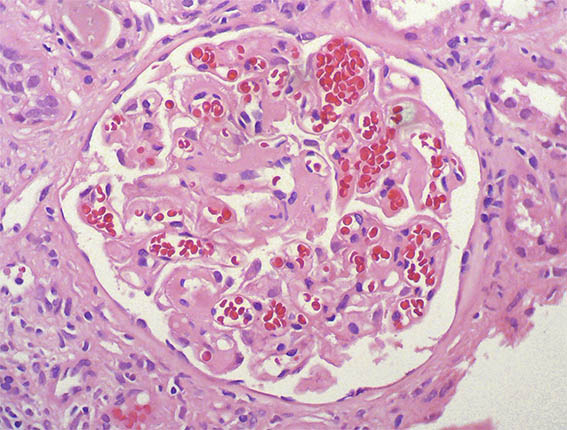

Figura 1.

H&E, X100.